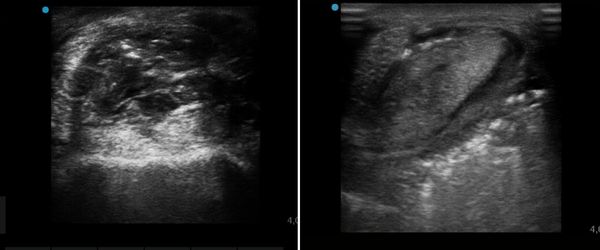

- progressiva riorganizzazione tendinea documentata ecograficamente

Andamento della guarigione

Durante il periodo di trattamento laser sono stati osservati:

- contrazione della ferita di circa 1 cm/settimana

- riduzione progressiva della zoppia

- formazione di tessuto di granulazione regolare e stabile

Un elemento clinicamente significativo è stato il rallentamento della guarigione dopo la sospensione della laserterapia, insieme alla ricrescita del pelo limitata alle aree trattate con laser, suggerendo un possibile effetto sulla qualità del tessuto rigenerato.